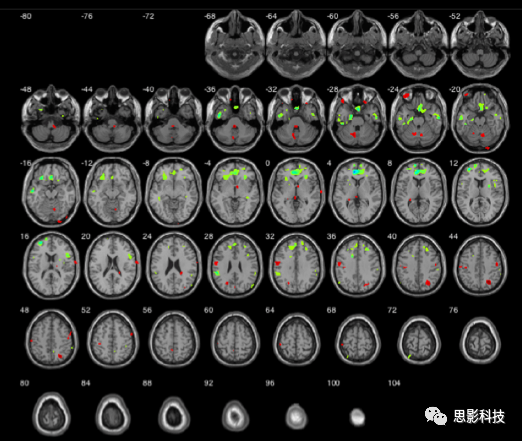

1.fMRI指標(biāo)。fMRI(功能磁共振)數(shù)據(jù)經(jīng)過(guò)時(shí)間層校正、頭動(dòng)校正、空間標(biāo)準(zhǔn)化、降噪等預(yù)處理步驟后,可計(jì)算ALFF(低頻振幅)、ReHo(局部一致性)、FC(功能連接)、VMHC(鏡像同倫功能連接)等指標(biāo)。以上指標(biāo)可以在體素水平計(jì)算。

圖示.fMRI指標(biāo):ReHo(左)與ALFF(右)

2.sMRI指標(biāo)。sMRI(結(jié)構(gòu)磁共振)數(shù)據(jù)經(jīng)分割后,可計(jì)算灰質(zhì)體積/密度、白質(zhì)體積/密度等指標(biāo);也可計(jì)算皮層厚度、皮層局部回指數(shù)等指標(biāo)。以上指標(biāo)可以在體素/頂點(diǎn)水平計(jì)算。